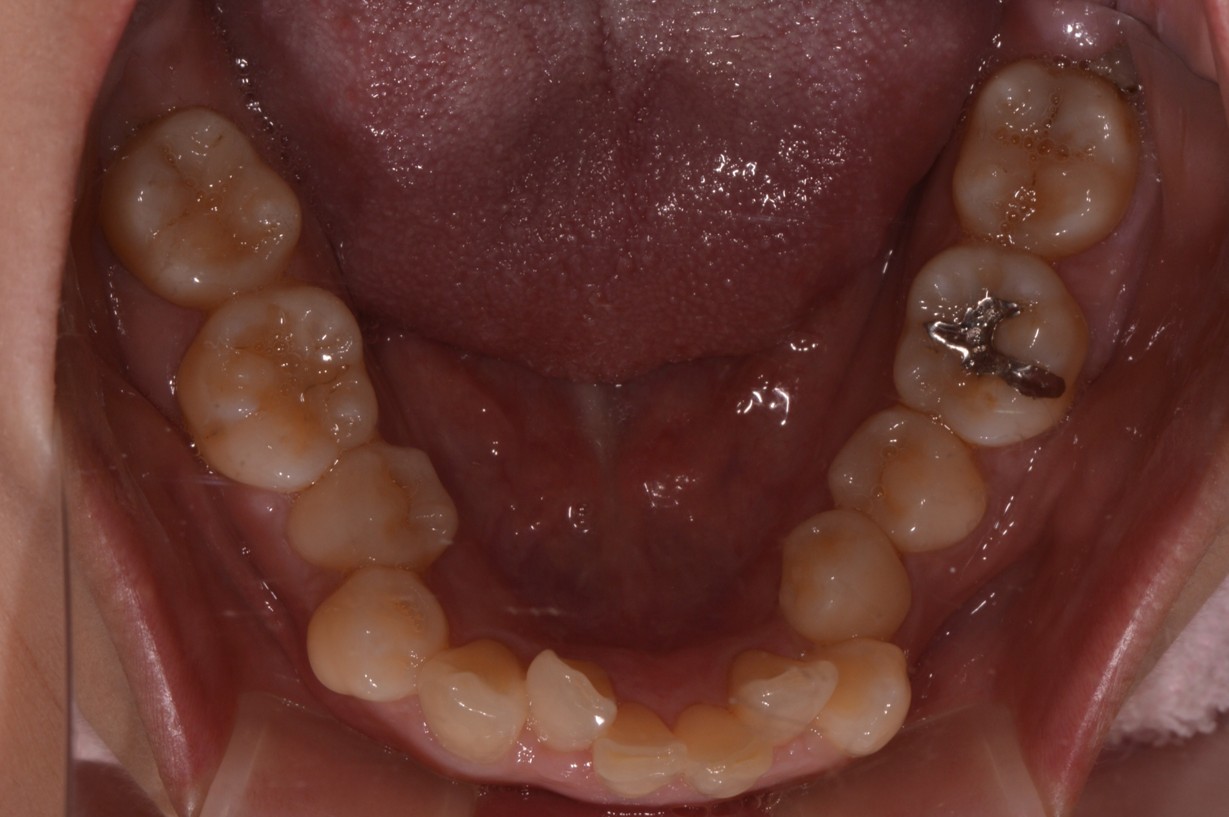

症例1

| 項目 | 詳細 |

|---|---|

| 患者様データ | 30代 女性 |

| 来院時の主訴 | 「上下のガタガタ歯並びと噛み合わせが気になる。」 |

| 矯正法 | 上の歯2本を抜歯しての矯正 |

| 通院期間 | 2年9ヶ月 |

| 治療費 | 総額:1,070,000円(税抜) 【内訳】 精密検査50,000円、メタルワイヤー矯正800,000円、月に1度の調整料5,000円、後戻り防止のリテーナー35,000円×2 |

| リスクと副作用 |

①歯を動かす事による痛みがあります。また、装置に慣れるまでは、口内炎ができやすいです。 ②歯肉が退縮するリスクがあります。装置が全ての歯に付くので、ハミガキが難しくなります。 ③長期的なメインテナンスが必要 |

| ここがこだわりのポイント!☝ |

この患者様の場合、歯並びのガタガタが強かったことや、抜歯したスペースを埋めるのに時間がかりました。ホームケアも大変だったと思いますが、とてもきれいな歯並びに改善することができました。 |